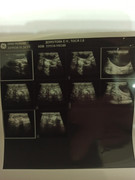

Сделали повторное узи 22.11. 2024 (первое было 09.11.2024). Высылаю фото и заключение.

Теперь ставят гидрометру и эндометрит. По мочевому мочекаменную.